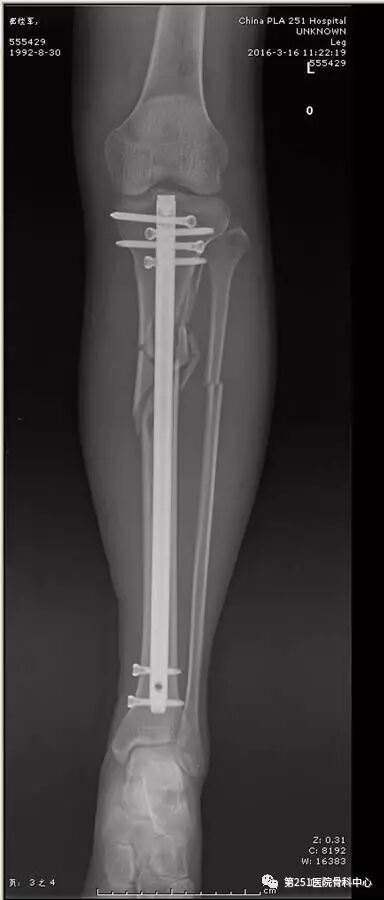

病例1:男性,40岁,车祸伤,胫腓骨多段骨折。

![]()